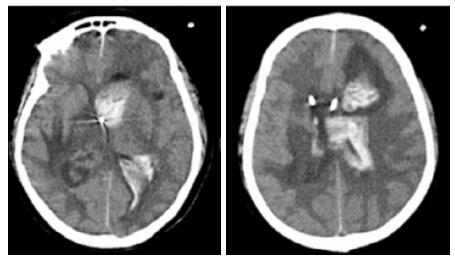

| A:右侧丘脑、左侧岛叶病变,伴脑室扩张;B:双侧脑室钻孔引流术后改变,脑室扩张较前(2019-09-29)好转,右侧丘脑、左侧岛叶病变伴出血 图 2 患者2019-09-29头颅CT平扫(A)和2019-09-30头颅CT平扫(B) |

转入ICU后呼吸机辅助通气、甘露醇100 mL/8 h静滴脱水、头孢呋辛1.5 g/12 h静滴抗感染,肠内营养等支持治疗。当晚血常规:白细胞13.3×109/L,中性粒细胞百分比85.3%,C反应蛋白17.1 mg/L,降钙素原0.64 ng/mL。脑室外引流术后次日血化验:白细胞16.6×109/L,中性粒细胞百分比92.8%,C反应蛋白78.4 mg/L;从脑室外引流管留取脑脊液检验:有核细胞6×106/L,红细胞1 960×106/L,蛋白含量1.717 g/L,葡萄糖4.72 mmol/L,细菌培养阴性,涂片未找到细菌;复查头颅CT示:脑室扩张好转,右侧丘脑、左侧岛叶病变伴出血(图 2);胸部CT示,两肺间质性肺炎下叶为著,较前(2019年6月21日)部分好转(图 3)。考虑到炎症指标升高,遂改哌拉西林他唑巴坦3.375 g/12 h静滴抗感染。此后经脑室外引流管反复留取脑脊液送检涂片及培养均阴性。术后第5天行“导航下立体定向颅内病灶活检术+双侧omaya囊置入术”,术中穿刺液呈黄色黏稠脓性,考虑脑脓肿,留取脓液送高通量测序(next-generation sequencing, NGS),并升级为美罗培南2 g/8 h联合利奈唑胺0.6 g/12 h静滴抗感染治疗。术后第7天患者突发血压升高、瞳孔不等大,昏迷程度加深;急查头颅CT示,双侧脑室钻孔引流术后改变,双侧侧脑室引流管走形区出血伴血肿形成;右侧丘脑区积液、积血,双侧脑室积血新发(图 4),甘露醇加量至250 mL/8 h联合地塞米松5 mg/6 h静滴加强脱水;当日术中脓液高通量测序结果回报:皮疽诺卡菌(序列数52 867个)、支气管戈登菌(序列数10个)。确诊脑诺卡菌病,抗菌治疗方案改为亚胺培南西司他丁0.5 g/6 h静滴,联合利奈唑胺0.6 g/12 h和复方磺胺甲恶唑片(0.48 g/片)3片/6 h口服。此后患者仍伴低热,炎症指标呈上升趋势。术后2周患者再次突发血压升高、瞳孔不等大、对光反射消失、神志深昏迷,急查头颅CT示再发脑疝(图 5),急诊行“去骨瓣减压术+脑内血肿清除术”,术后患者仍呈深昏迷状态,双侧瞳孔散大、对光反射消失,次日自动出院。